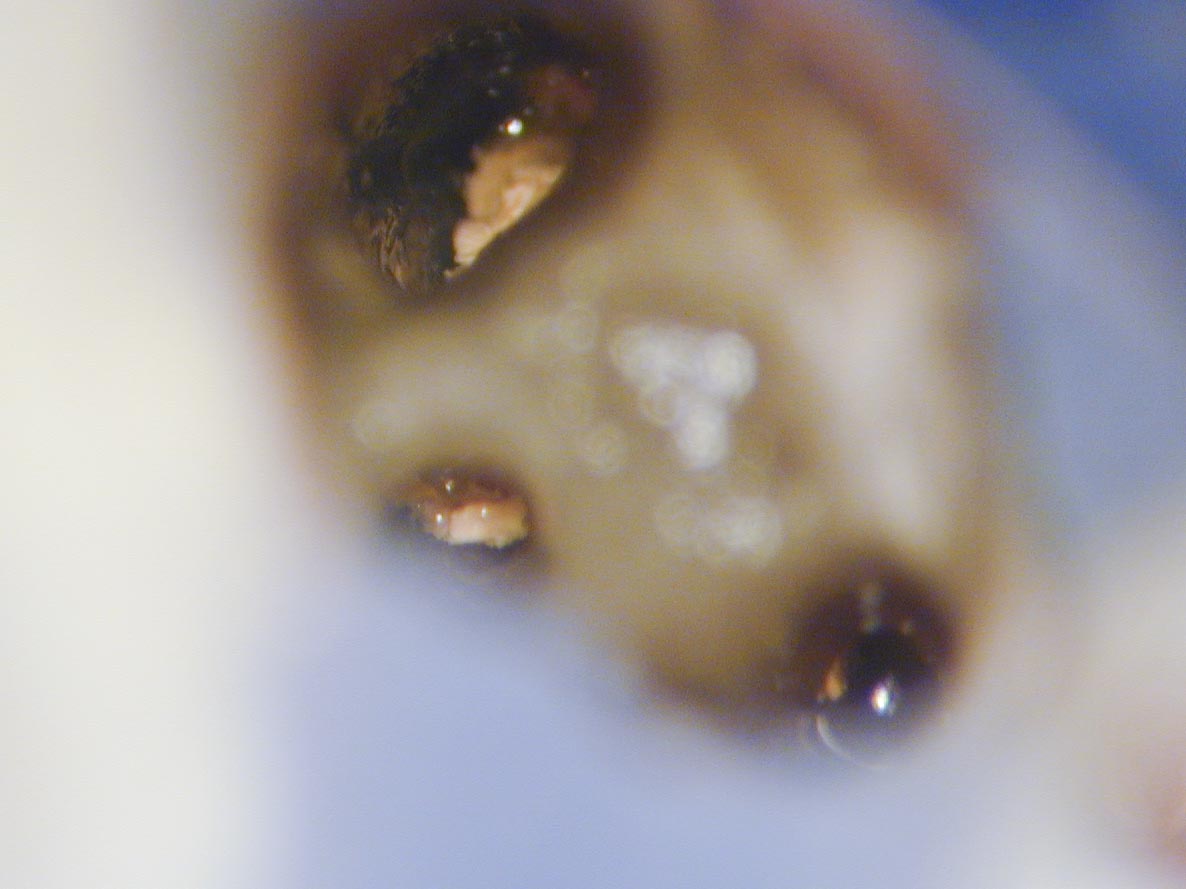

C Shape-2

C Shape Zahn 37